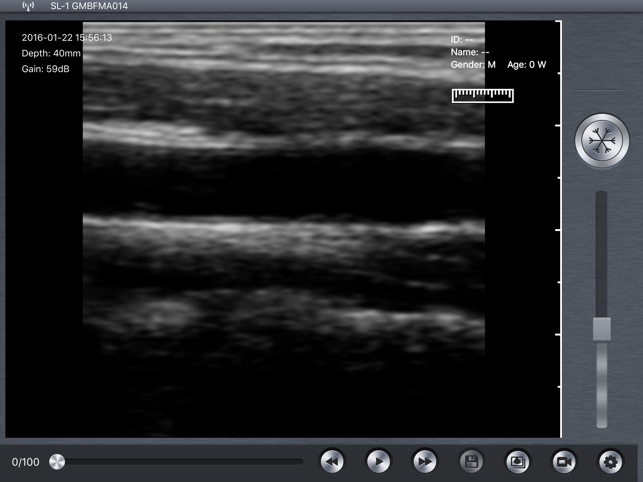

Wireless B-Scanner for Ultrasound Diagnose.

Wireless B-Scanner for Ultrasound Diagnose.